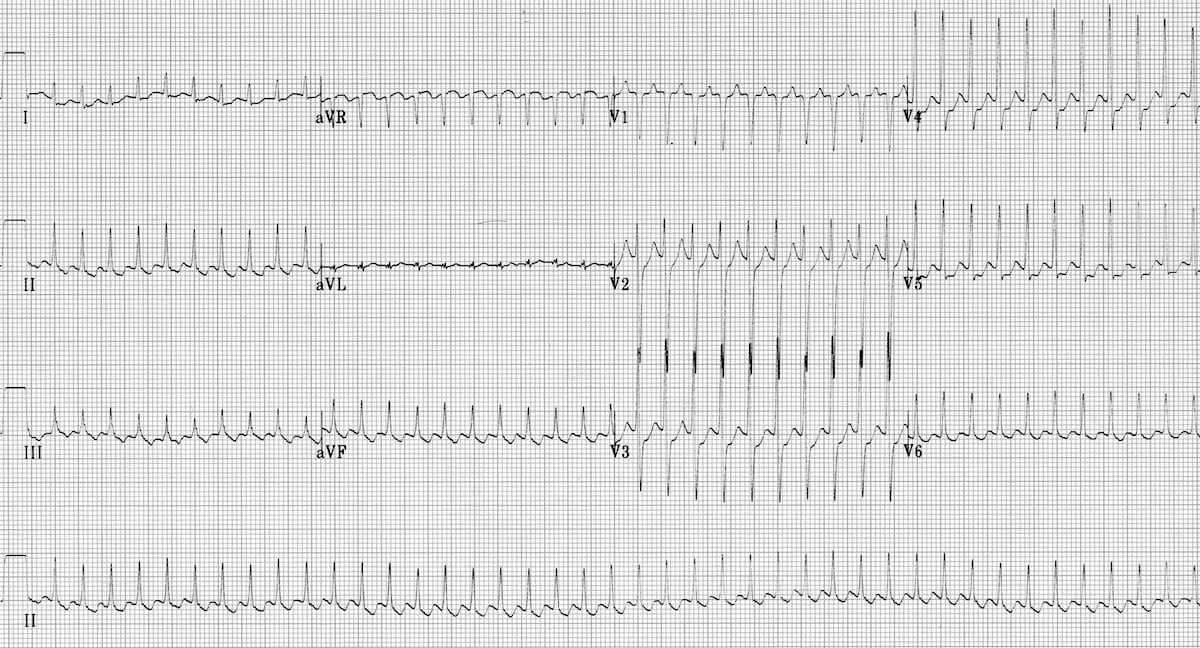

Example 3

Atrial flutter with 4:1 block

- There are inverted flutter waves in II, III + aVF at a rate of 260 bpm

- There are upright flutter waves in V1-2 (= anticlockwise circuit)

- There is 4:1 block, resulting in a ventricular rate of 65 bpm

- The relatively slow ventricular response suggests treatment with an AV nodal blocking agent